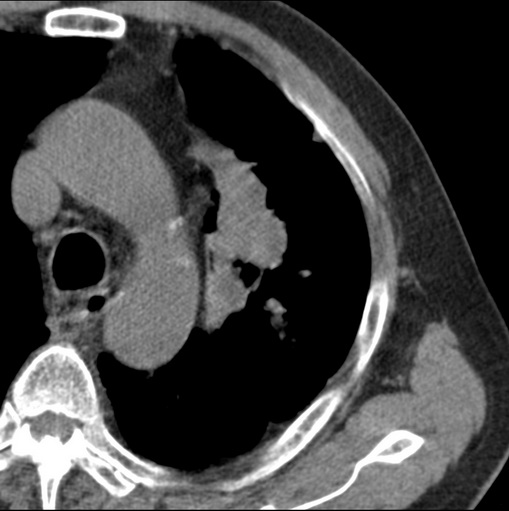

标题: CT25434:胸部CT增强扫描

男性患者 81岁 咳嗽 咳痰 咯血

考虑左上肺癌并阻塞性肺炎,左肺转移、左肺门及纵隔淋巴结转移。

肿块贴近左肺门,包绕左上肺动脉,形态不规则。肿块增强扫描中度强化。纵膈内主动脉弓左旁间隙、气管隆突前、下间隙见多枚淋巴结影。综上考虑左侧中央型肺癌可能性大。图片没有完整上传,尤其是左肺上叶支气管分支层面没有上传,因此不好判断是叶支气管中断还是段支气管中断。另外,下图红色部分所示是“黏液支气管征”吗?